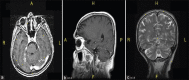

Intravascular papillary endothelial hyperplasia (IPEH) also known as Masson's tumor, is a benign, slow growing, vascular lesion which is seen very rarely and only a few cases have been reported intracranially in the literature. It has been reported at many sites, but the posterior fossa involvement is very rare. The preoperative diagnosis is very difficult, as there is no enough cases to achieve a clear understanding about the details of its radiological findings. Differential diagnosis have to be made especially from angiosarcoma and meningioma. It is curable by total surgical removal. In this article we presented the characteristic clinical, radiological, perioperative and pathological findings in a case of IPEH in an unusual location, origin and behavior. To best of our knowledge, we presented the first case of IPEH originating from tentorium.